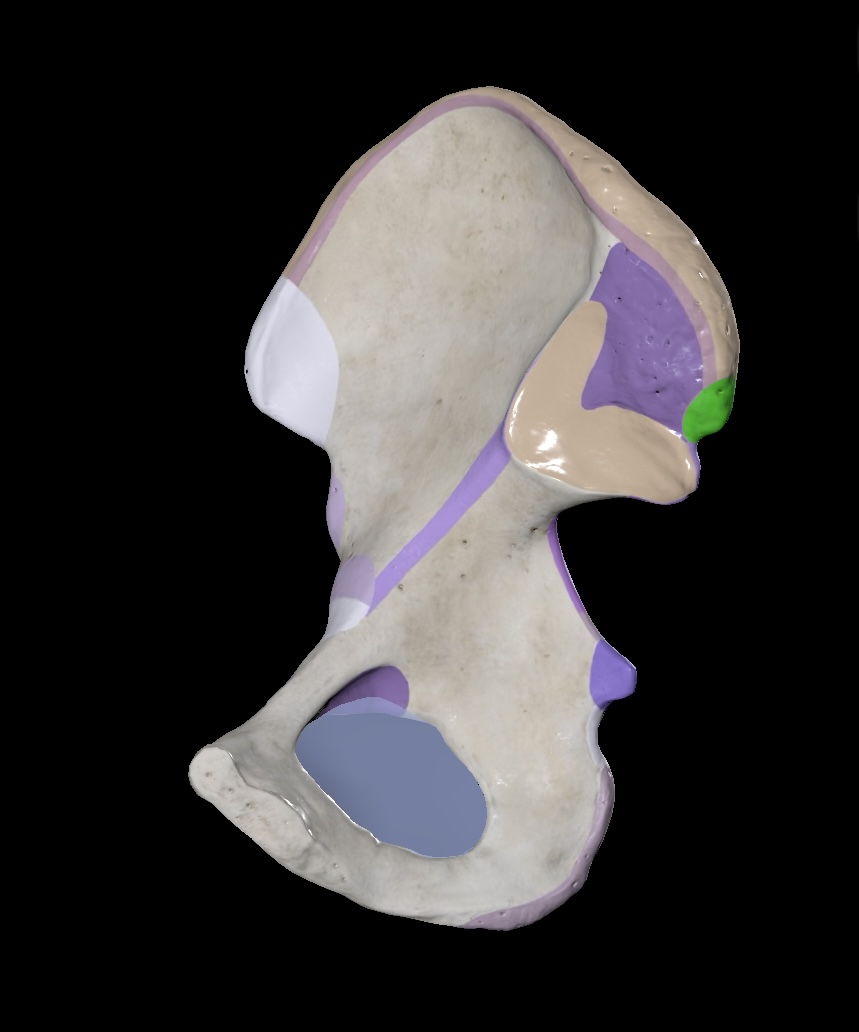

Illium

Ischium

Pubis

Ischial Spine of Ischium

Iliac Tuberosity of Illium

Anterior Superior Iliac Spine

Anterior Inferior Iliac Spine

Posterior Superior Iliac Spine

Posterior Inferior Iliac Spine

Iliac Crest

Acetabulum